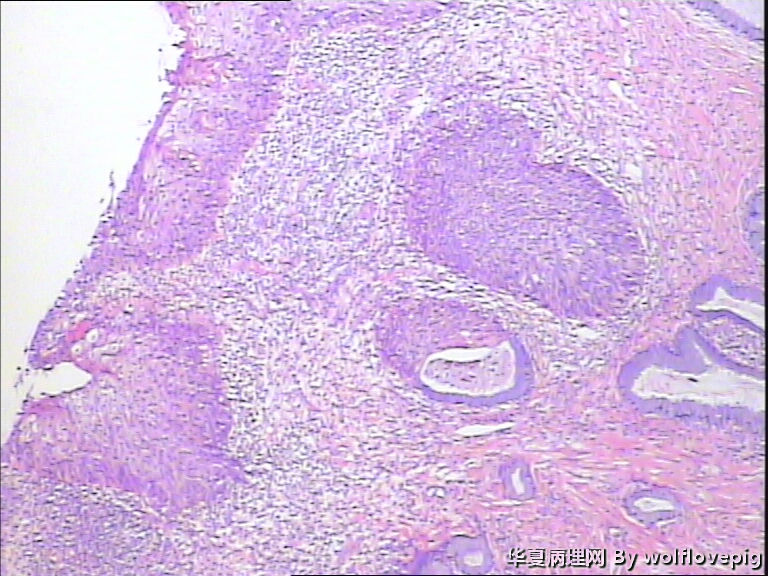

求助,宫颈!

37y

CIN3累腺

CINIII累及腺体